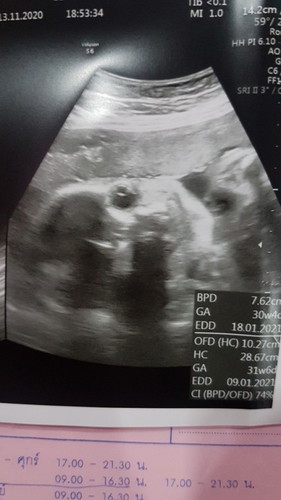

30w1d

กำหนดคลอด24 มกราค่ะ ลูกสาวว 30w6d